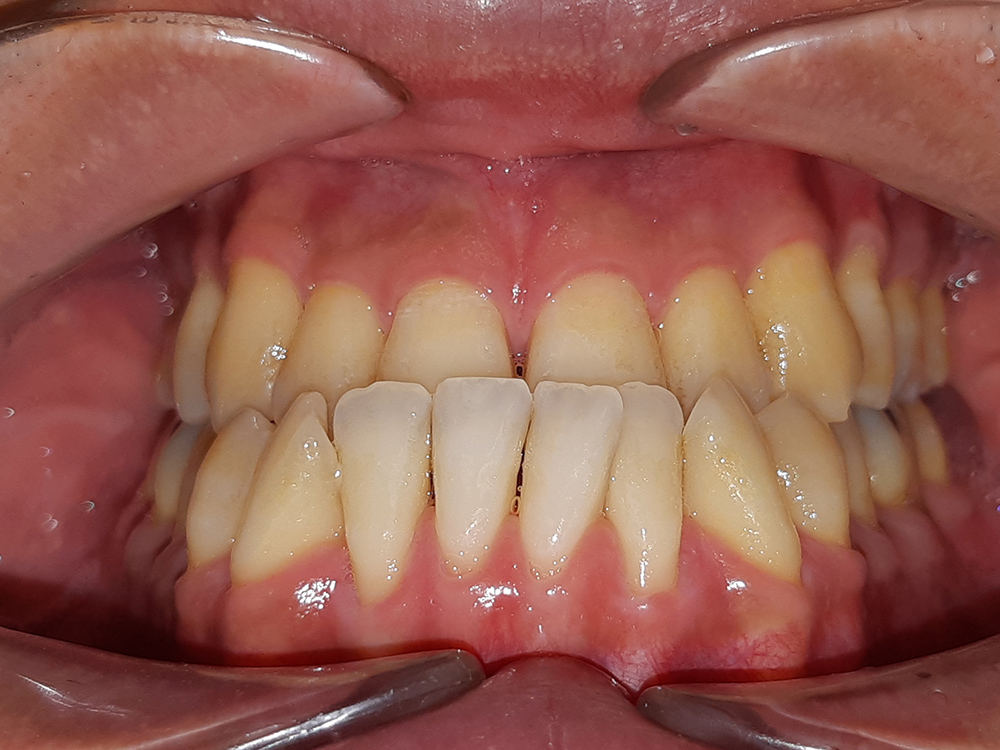

案例:不開刀齒性戽斗前後比較

4. 牙齒過度磨耗

長期咬合不正是牙齒磨耗的主因,牙齒會從牙齒邊緣或切端開始有缺角,牙齒的琺瑯質會變薄或透明,當牙齒磨耗過度造成牙冠損壞,患者有時就會感到牙齒敏感或痠痛,此時就會需要修復損壞的牙齒,通常以補牙或是假牙的方式保護,若能及早進行矯正治療,改善咬合問題,便能避免牙齒長期過度磨耗。